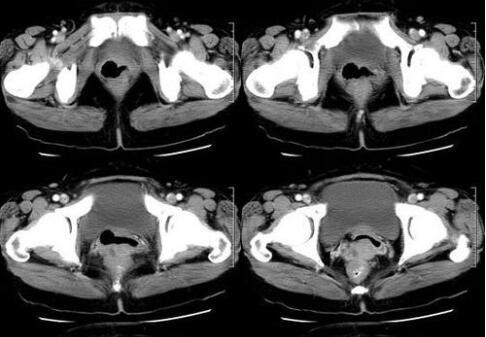

陈女士说,相比其他中晚期患者,她已经幸运很多了。起码是早期发现,生存希望还很大。在确认病理结果后,陈女士迅速和主治医生敲定了手术方案。手术很顺利地切除了癌变卵巢,保留子宫和对侧卵巢,且术后CT复查也显示她的体内已经没有任何病灶了。

我的的治疗团队细致地为她制定了个性化的治疗方案。陈女士开始接受每2周1次的NKT细胞治疗。12月9日,陈女士第一次接受NKT细胞治疗时淋巴细胞百分比是14%,但在12月22日接受第2次NKT细胞治疗后,淋巴细胞百分比上升至22%,接受第4次NKT细胞治疗后,数值已上升至至35%。